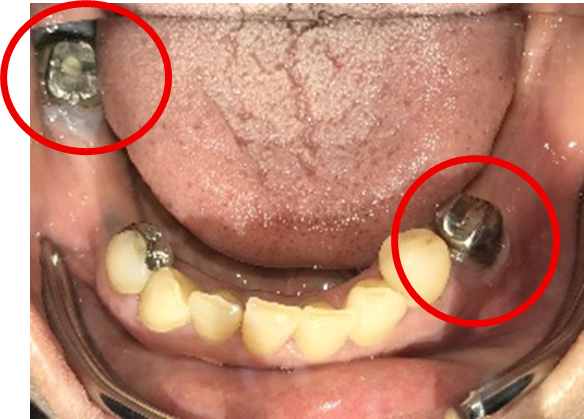

Before

▼初診時に使用していた部分入れ歯を装着したところ

▼インプラント埋入前